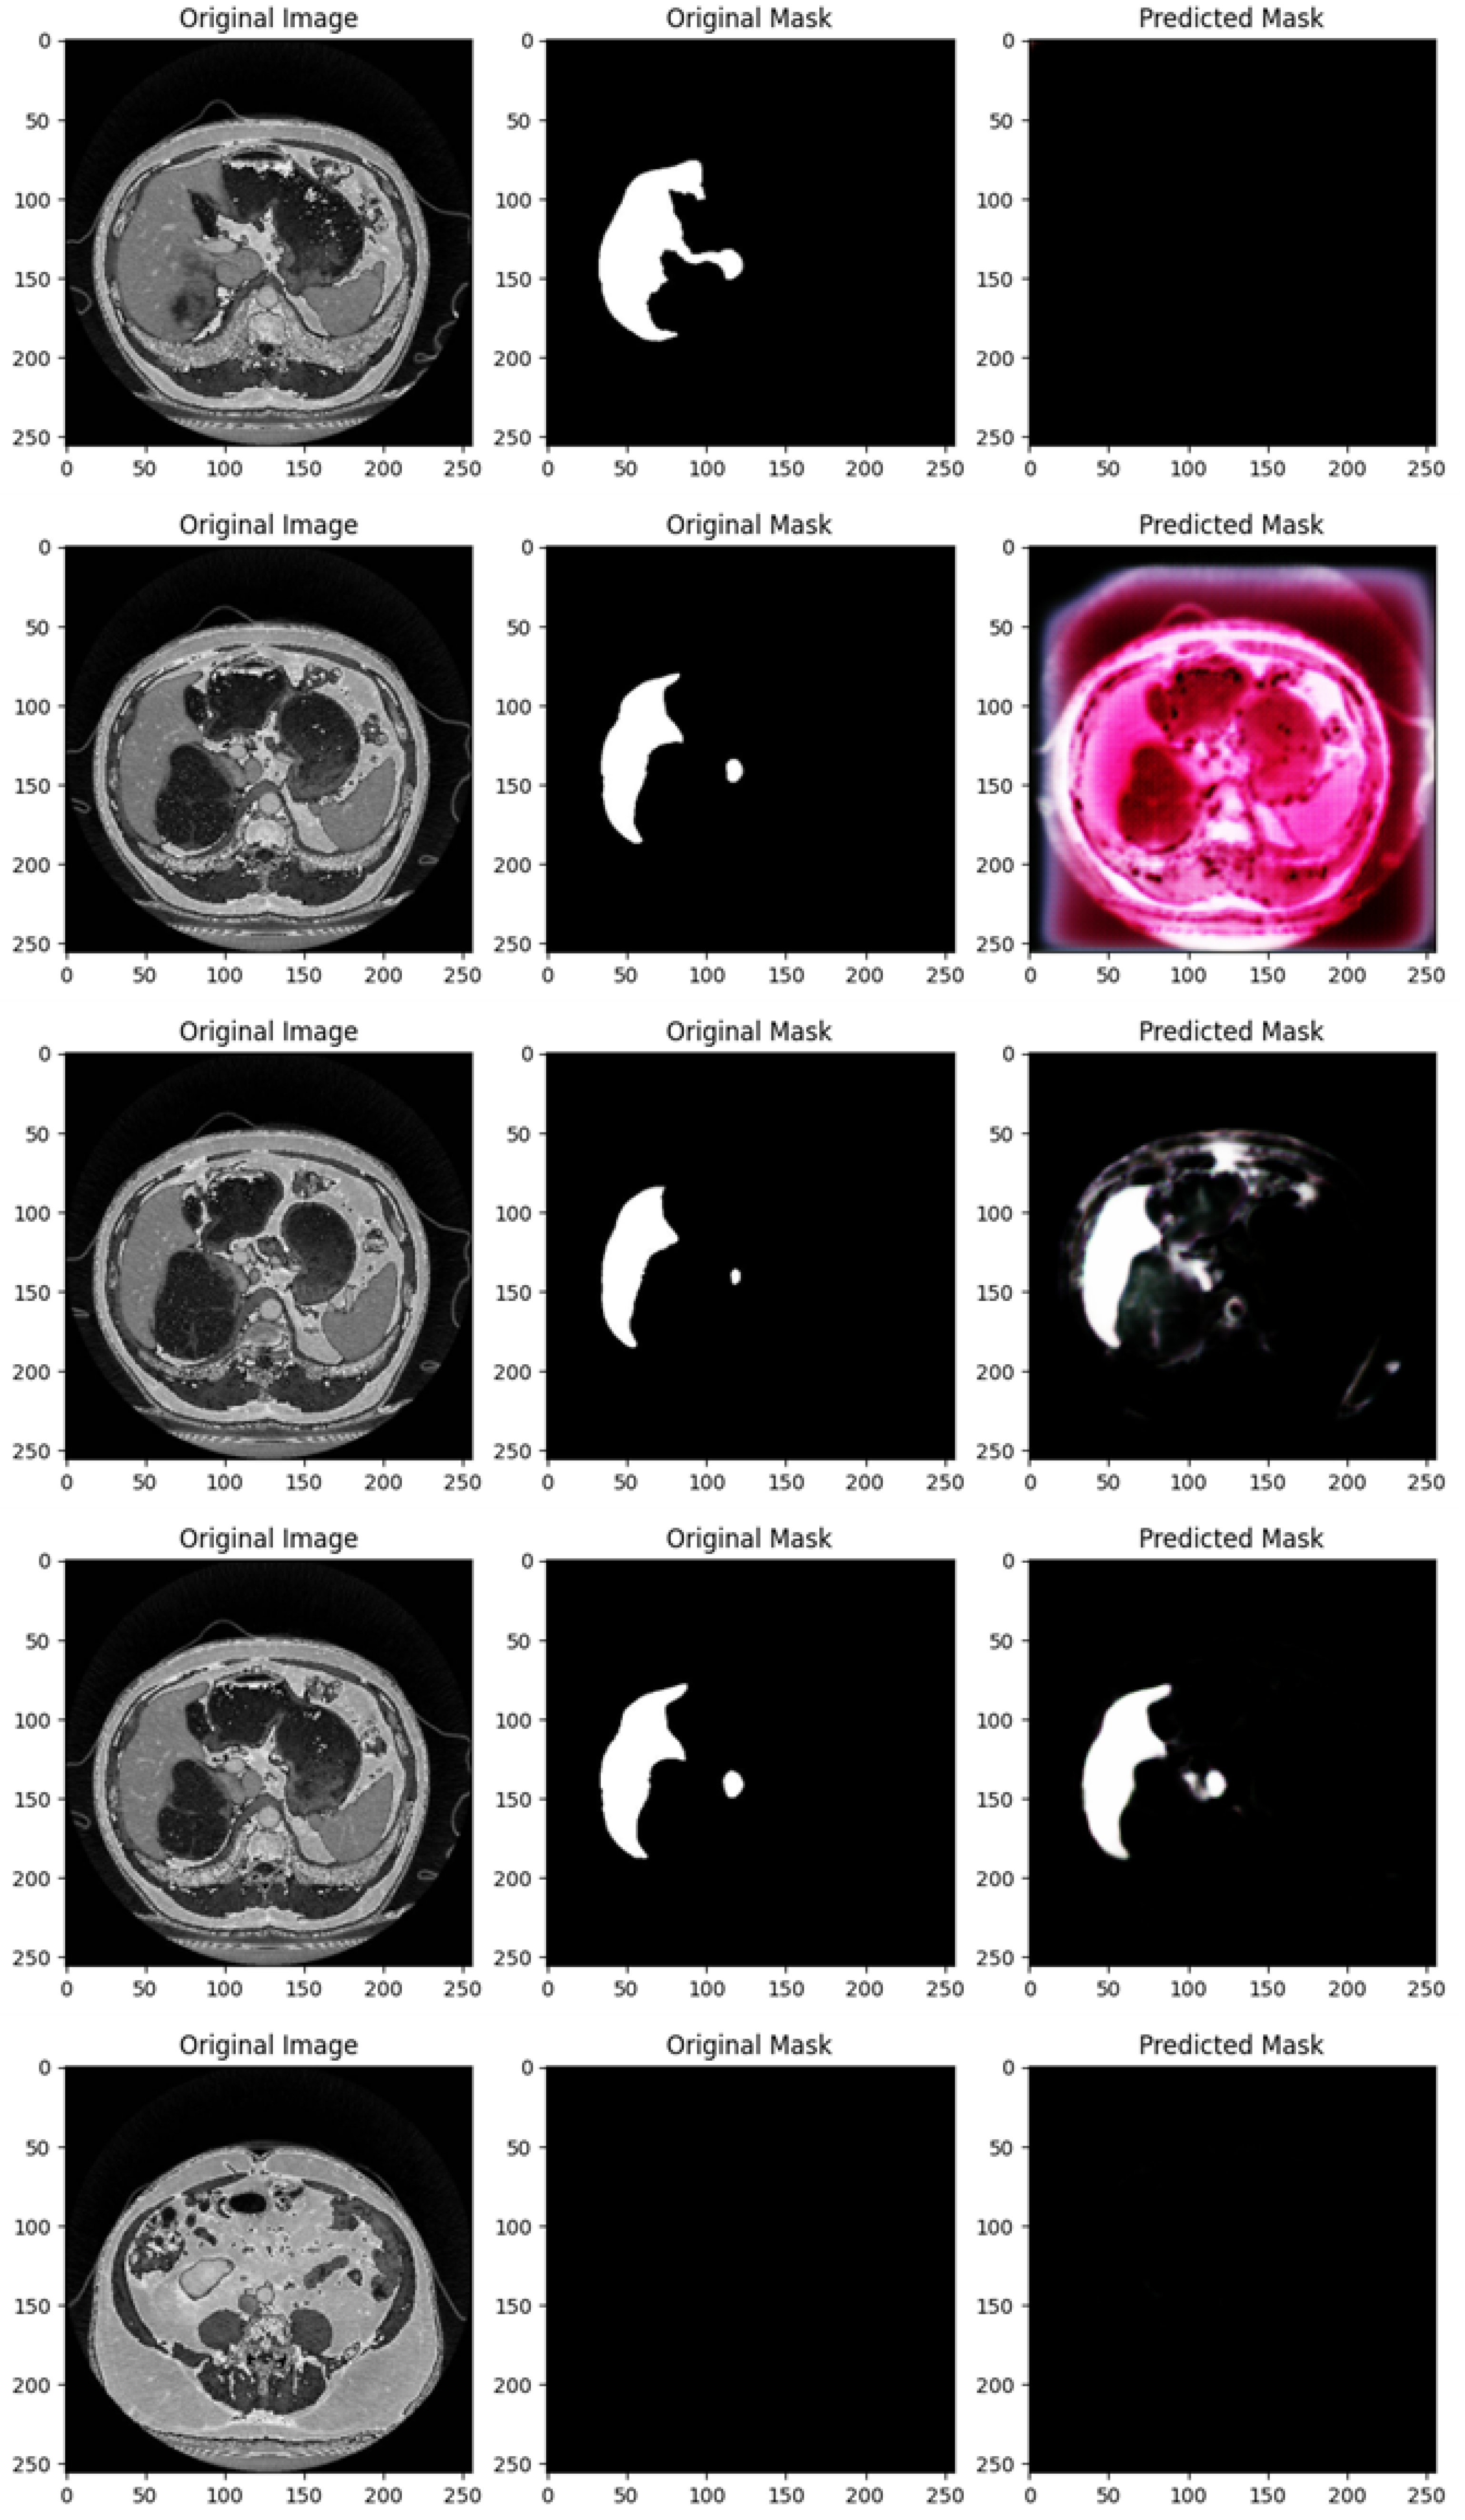

Figure 5 shows the segmentation capabilities every 25 epochs (for the first 100 epochs) of the U-Net model trained with the DII dataset.

Figure 5 shows, similarly to Figure 4, for different epochs, a set of images with the related segmentation mask predicted at a certain epoch. In particular, Figure 5 shows the original images, original masks (i.e., the ground truth) and the predicted masks generated by a U-Net network trained for different numbers of epochs (1, 25, 50, 75, and 100 from top to bottom).

We provide a detailed analysis for the several masks generated for each epoch considered in Figure 5:

At 1 epoch, the CT scan shows an upper abdominal slice, and the original mask clearly marks a white region, which appears to be a segment of an organ, likely the spleen or liver. However, the predicted mask is empty, suggesting that the U-Net model, at this early stage of training, has not yet learned to recognize and predict the target region. This is typical for early-stage training models and aligns with the expected behavior of the model at this point.

At 25 epochs, the model begins to show some improvement. The original image is another abdominal CT slice with visible internal organs, and the target organ (likely the liver or spleen) is again demarcated in white. The predicted mask at this stage is partial and somewhat noisy, lacking clear boundaries. While the shape begins to resemble the organ, the prediction is still underdeveloped, which is characteristic of intermediate-stage training.

By 50 epochs, the model’s performance has significantly improved. The original image is another CT scan slice showing a similar anatomical view, and the organ of interest is clearly outlined in white. The predicted mask captures a much larger portion of the target region, and the segmentation is more refined. Despite this progress, some blurred edges and noise remain, indicating that the model is still refining its boundaries, which is expected as it continues to learn.

At 75 epochs, the model achieves a high level of accuracy. The original image is another abdominal CT slice, and the target organ is clearly marked with a smaller, localized region. The predicted mask closely resembles the original mask, with distinct boundaries and minimal noise compared to earlier stages. At this point, the U-Net model has learned to accurately isolate and segment the region of interest with greater precision.

At 100 epochs, the model demonstrates very high accuracy. The original image is an upper abdominal CT scan, and the original mask again marks the target organ with clear boundaries. The predicted mask is almost identical to the original, with sharp boundaries and very little noise or extraneous segmentation. This shows that by 100 epochs, the U-Net model is able to predict the target region with high fidelity and precision.

As shown from Figure 5, as the number of epochs increases, the U-Net network shows clear improvement in segmenting the liver organ. At 1 epoch, the model fails to make any predictions. By 25 epochs, it begins to recognize some parts of the organ, though the segmentation is noisy and incomplete. From 50 epochs onward, the segmentation becomes progressively more accurate, with the U-Net model capturing more of the organ’s shape and reducing background noise. At 75 and 100 epochs, the predicted masks closely match the original masks, showing the model’s capability to accurately segment the target region after more extensive training.

With increased training, the model becomes progressively better at recognizing and segmenting the target region. By 100 epochs, the model reaches a stage where the predicted masks are highly accurate, closely mirroring the original masks with minimal noise and strong boundary definition.